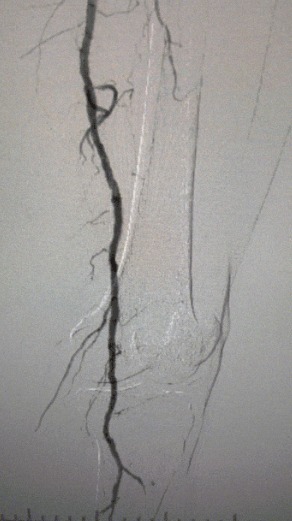

Клинические выводы

· Физическое обследование: слабые импульсы бедренной кости; отсутствие импульсов подколенных и спинного ног; изъязвление на первом левом пальце ноги; некроз на первом и втором пальцах правой ноги

· Предоперационная визуализация: тяжелый диффузный кальцинированный стеноз в двусторонних артериях нижних конечностей.

Хирургический результат

Пост-процедура, артериальный стеноз улучшился значительно, кровоток увеличился, и температура кожи поднялась. Послеоперационных осложнений не произошло. И пациент, и хирургическая команда были очень довольны результатами.